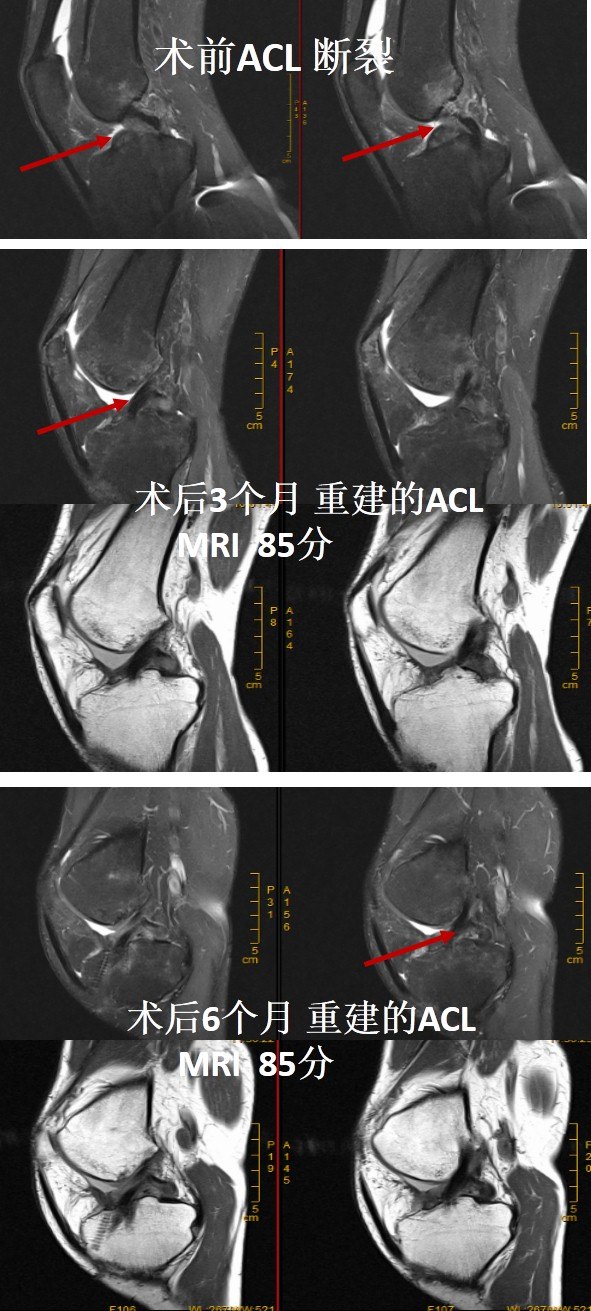

也有些患者在前交叉韧带重建术后3个月到半年,韧带已经塑形十分完好!

使用自体肌腱重建ACL后,移植物一般要经历缺血坏死、血管再生、细胞长入、细胞增殖和韧带塑形等四个主要过程,最终肌腱坏死后有重新成活,变成“ACL”。在人体体内肌腱塑形成ACL的过程可分为:早期阶段(0~6个月)、塑形阶段(6-12个月)和成熟阶段(12-24个月)。深刻认识这个过程有助于指导患者术后的康复,我们的观点认为,单纯ACL重建后,3个月内需要带护具慢走,6个月后可以快走,1.5年~2年后才可以恢复体育运动,在随访的每一个时间点都需要进行体格检查和核磁共振(MRI)进行评估膝关节的稳定性和韧带塑形情况。